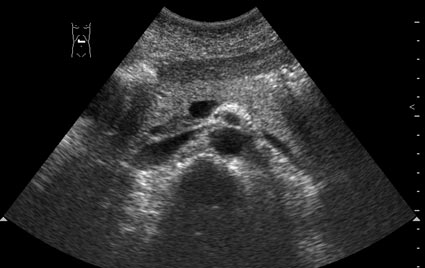

Гипостеатоз крючковидного отростка панкреас

Пациент 35 лет, без жалоб, профилактический осмотр.

По задней поверхности головки панкреас имеется участок сниженной эхогенности.

Цитата: "The hypoechoic area is located posteriorly in the head and typically shows a straight and clear demarcation. This demarcation line corresponds to the level of fusion between both embryonal ventral and dorsal portions of the pancreas. In accordance with the structural differences that have been described between the embryologically derived ventral and dorsal pancreatic portions , has shown that the ventral portion of the pancreas may appear hypoechogenic because more rich of fatty tissue compared to the dorsal portion."

считаю вариант нормы,так выглядит процессус унцинатус в норме